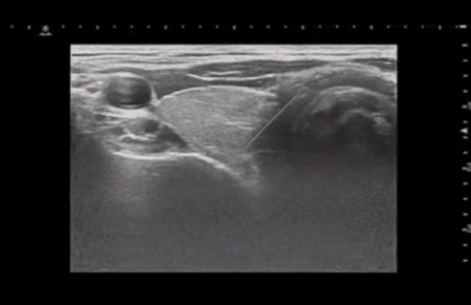

本技術開發一套結合延展實境(XR)與AI即時輔助之醫療模擬系統,用於訓練超音波導引下之內分泌手術與侵入性操作。系統具備高度擬真、多使用者協作、觸覺回饋與錯誤偵測能力,可加速學習曲線,提升訓練效率與病患安全。